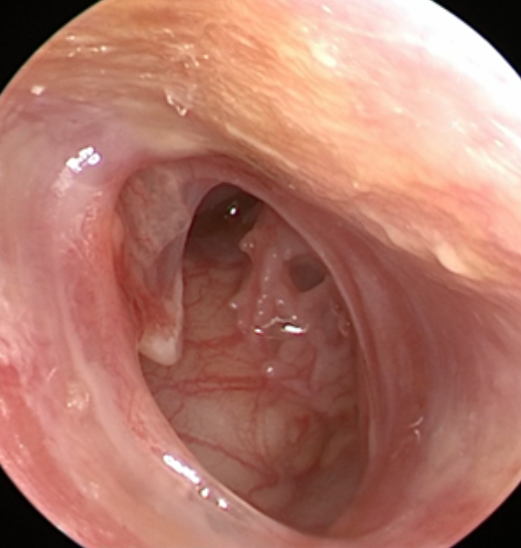

耳鼻喉科新开展的耳内镜下鼓膜修补术是运用耳内镜,通过外耳道的自然通道就可以完成手术,手术一般采用颞肌筋膜或耳屏软骨-软骨膜复合物作为修补材料,手术成功率98%以上。

手术从外耳道自然通道进入,耳廓周围没有其他手术切口,手术时间短、出血量极少,做到真正的微创、美观;术后外耳道只需轻微填塞,没有明显疼痛。

正常鼓膜

中耳炎鼓膜穿孔